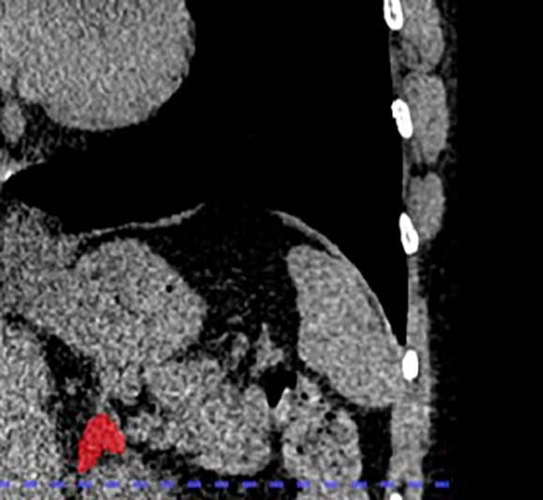

Lead author of the new study, Dr. Elena Ghotbi, developed and trained a deep learning model to measure adrenal gland volume on existing CT scans.

The team applied their deep learning model to the CT scans to segment and calculate the volume of the adrenal glands.